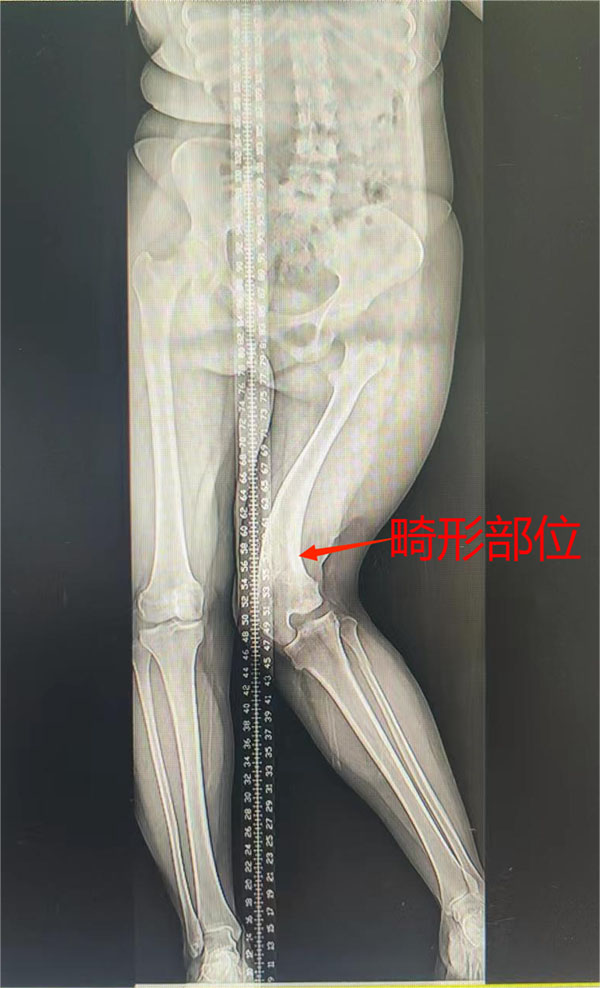

第一步:行左股骨远端截骨+Illizarov外固定架固定矫形延长术,术后通过每日定量的调整Illizarov外固定架上的延长杆,达到矫正肢体畸形的目的(此过程大概需要4-6个月)。

▲术前畸形,拆除外固定架,钢板内固定